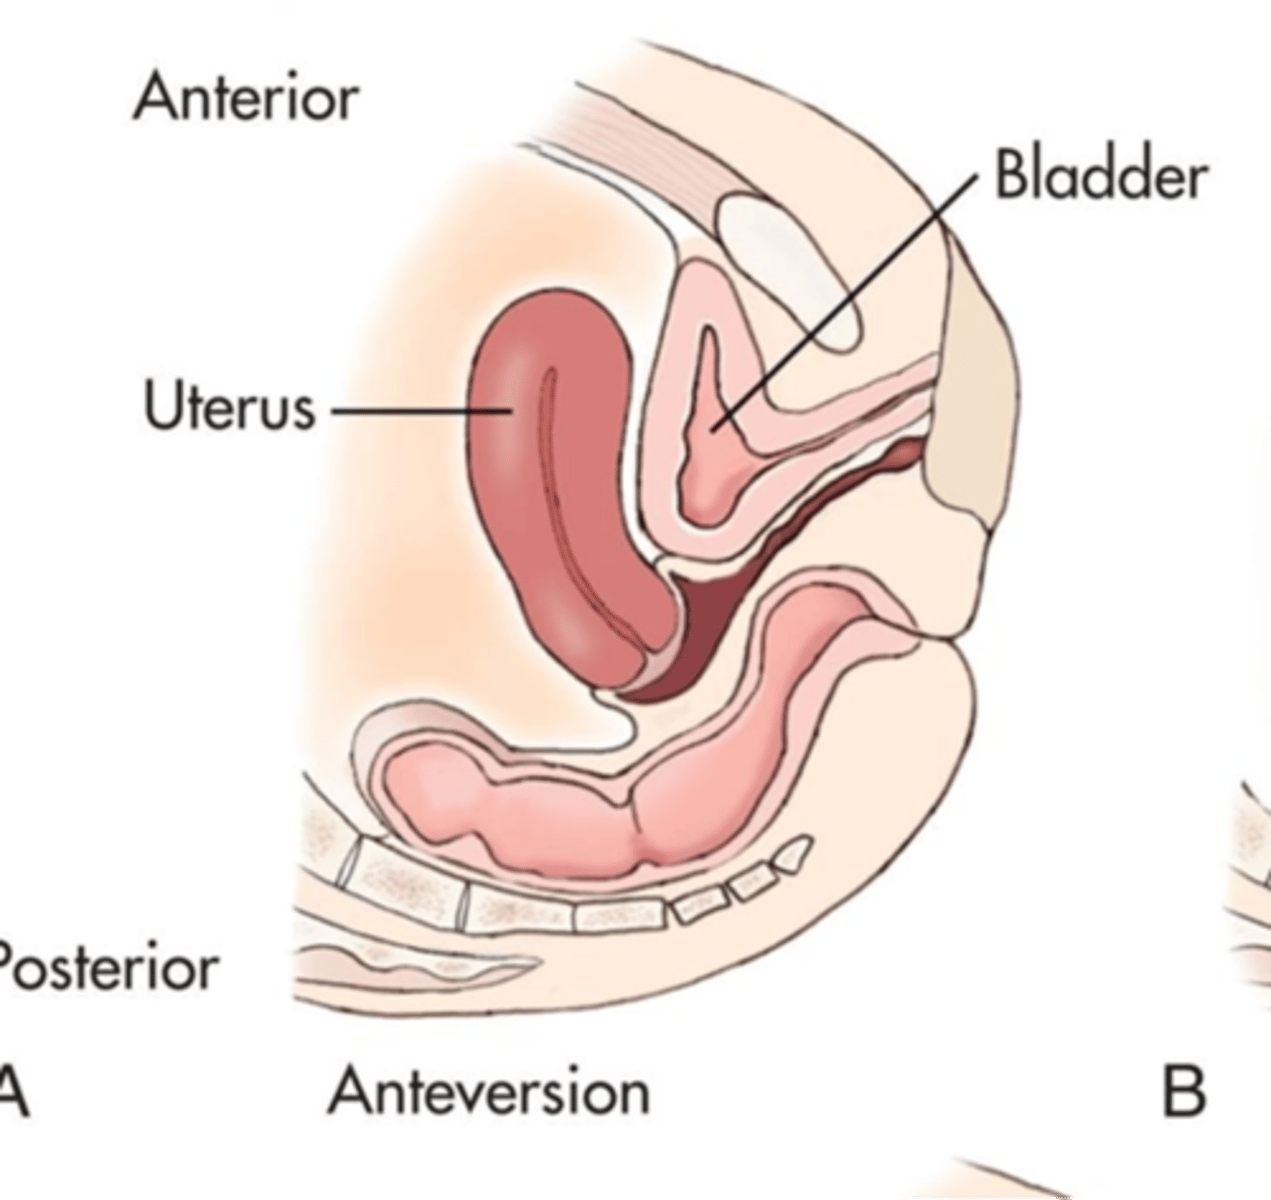

Verted = ___

Flexed = ___

tilt

bend

What is the most common uterine position?

anteverted

What is an anteverted uterus?

fundus and body tilt forward, cervix and vagina form 90 degree angle

What is an anteflexed uterus?

fundus and body bend forward, cervix and vagina form 90 degree angle